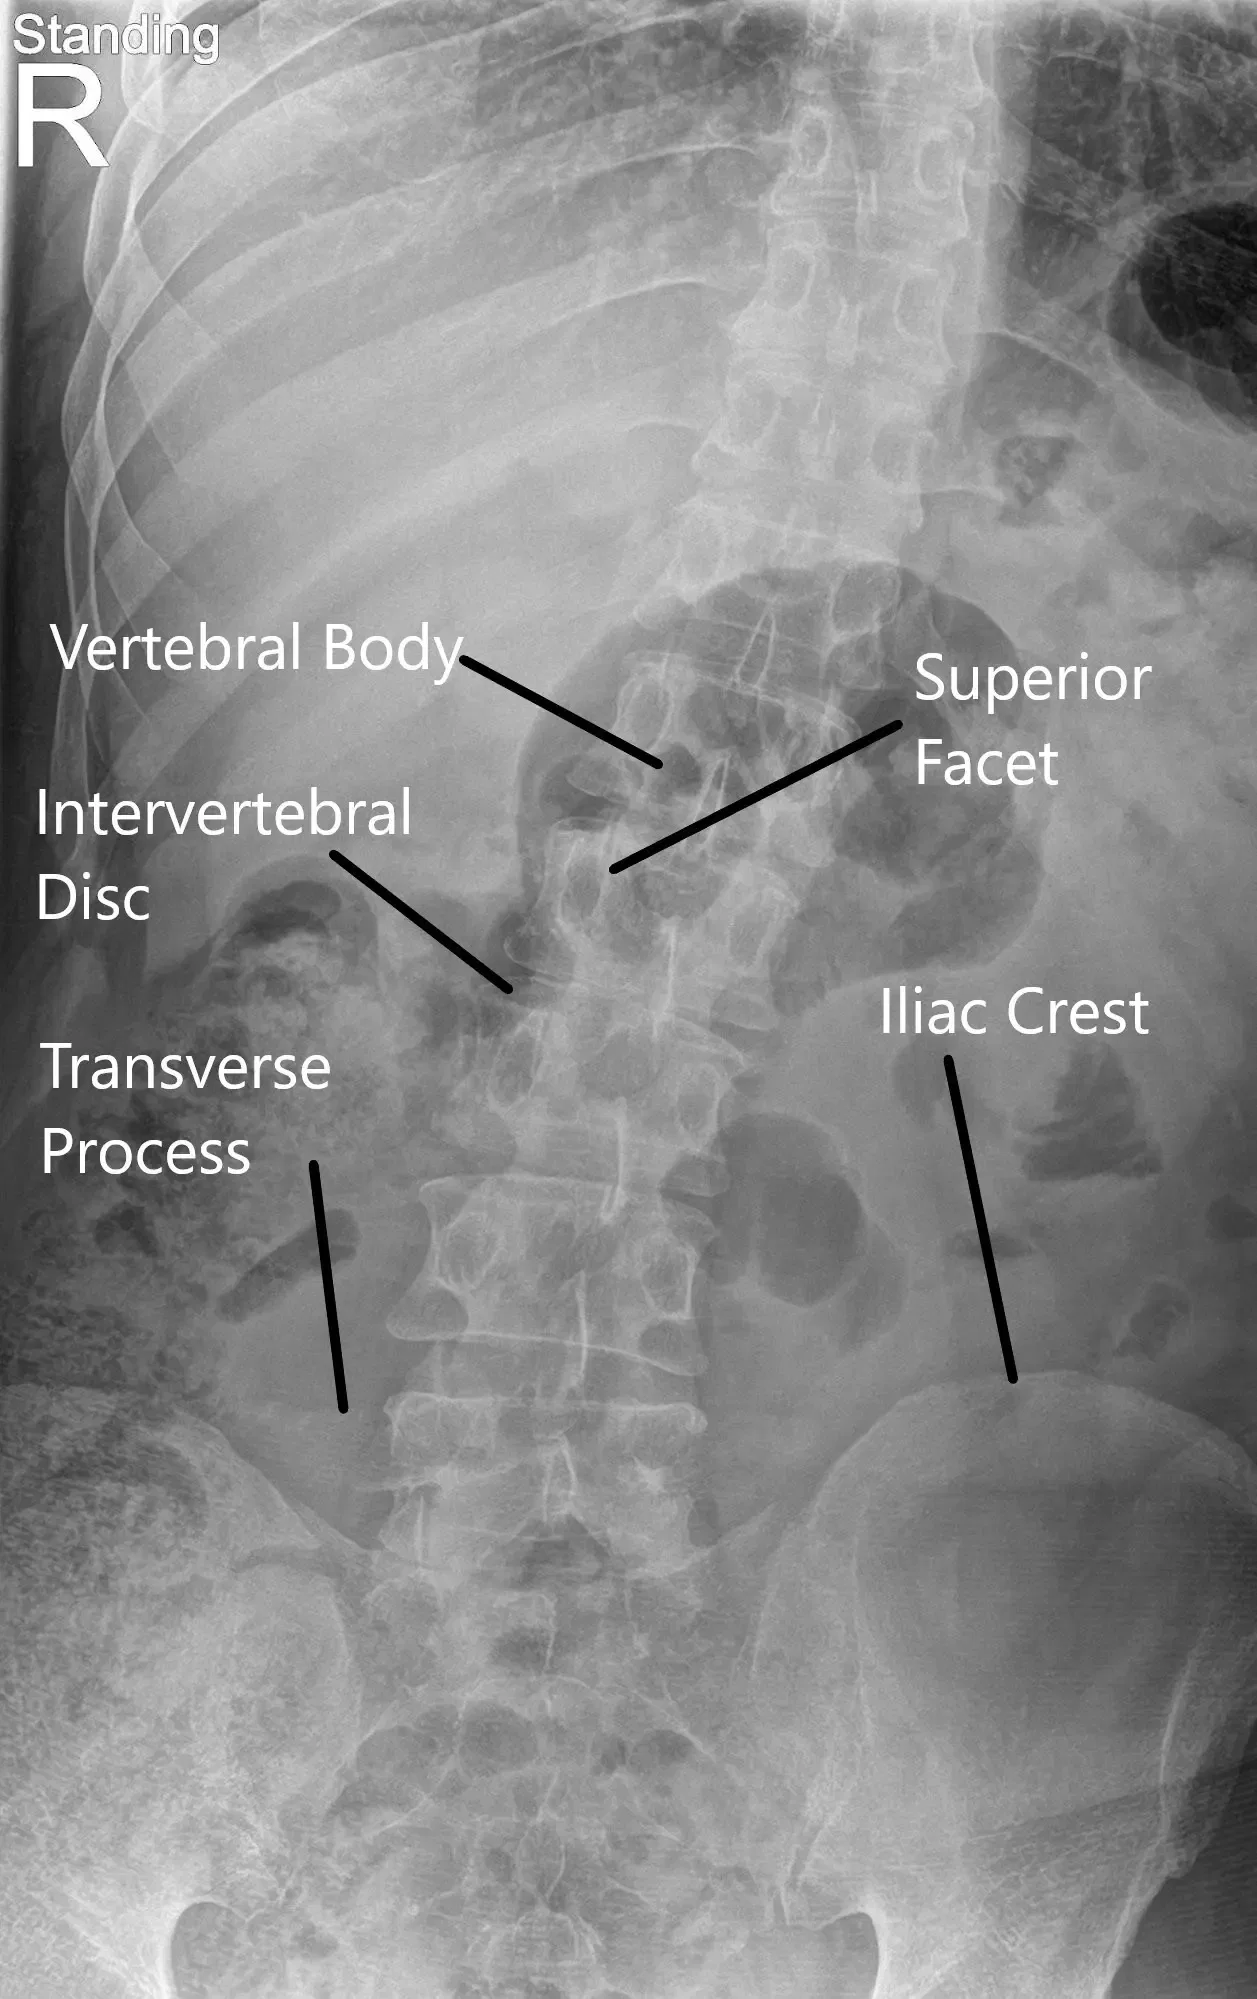

X-ray of the LS spine suggested degenerative changes and moderate dextroscoliosis.

LS Spine X-ray in AP and Lateral views.